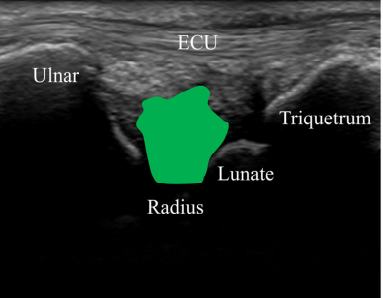

"첫째, '쿠션' 기능이 망가졌다는 것입니다."

TFCC의 핵심 부위인

삼각섬유연골(관절 디스크)은

손목의 충격을 흡수하는 쿠션입니다.

@ https://doi.org/10.3390/s22010345

건강한 손목은 새끼손가락 쪽으로 꺾을 때

이 쿠션이 압축되면서 면적이 넓어집니다.

정상적으로 펴지면서 충격을 흡수하는 거죠.

그런데 TFCC가 손상된 환자들은정반대였습니다.

새끼손가락 쪽으로 꺾을 때

오히려 이 쿠션이 쪼그라들면서

면적이 작아졌습니다.

쿠션이 제 역할을 완전히 잃어버린 겁니다.